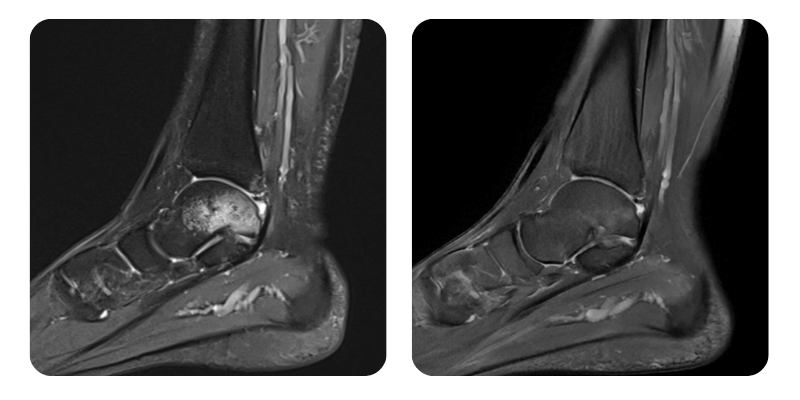

Vorher

Nachher

B.A.A., 25 Jahre – Postkontusionelles Knochenödem am linken Talus.

Diagnose: Postkontusionelles Knochenödem am linken Talus, Calcaneus und Os cuboideum sowie an den medialen und lateralen Malleolen; Ruptur des vorderen talofibulären Bandes links; Ödem des hinteren talofibulären Bandes und des tiefen Anteils des Deltabandes; Gelenkerguss.

Verlauf: Eine Reduktion des Ödems um ca. 90 % wurde festgestellt.